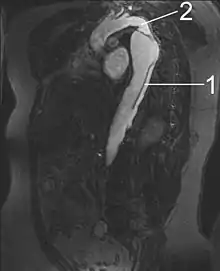

| Dissection of the descending part of the aorta (3), which starts from the left subclavian artery and extends to the abdominal aorta (4). The ascending aorta (1) and aortic arch (2) are not involved in this image. | |

- Aorta descendens with dissection

- Aorta isthmus

Magnetic resonance imaging (MRI) is also used for the detection and assessment of aortic dissection, with a sensitivity of 98% and a specificity of 98%. An MRI examination of the aorta produces a three-dimensional reconstruction of the aorta, allowing the physician to determine the location of the intimal tear and the involvement of branch vessels, and to locate any secondary tears. It is a noninvasive test, does not require the use of iodinated contrast material, and can detect and quantitate the degree of aortic insufficiency.

The disadvantage of the MRI scan in the face of aortic dissection is that it may be available only in larger hospitals, and the scan is relatively time-consuming, which could be dangerous in people who are already very unwell. Due to the high-intensity magnetic fields used during MRI, it cannot be used on individuals with metallic implants. In addition, some individuals experience claustrophobia while surrounded by the MRI magnet.